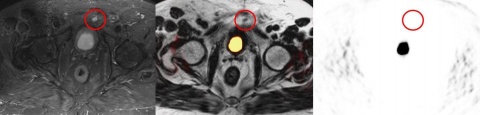

In der Literatur finden sich zunehmende Hinweise darauf, dass mit Hilfe der sog. PSMA PET eine weitere Steigerung der Diagnosesicherheit möglich ist. Das PSMA ist ein integrales Membran-Protein, welches in Prostatakarzinomzellen bis zu 1000-fach stärker exprimiert wird als in gesunden Prostatazellen. Die Expression ist insbesondere in höhergradigen Karzinomen bei einer metastatischen Erkrankung und in hormonrefraktären PCa gesteigert (Abbildung 1). Folgerichtig wurde das PSMA zu einem Target hochgradigen Interesses für die spezifische Bildgebung und Therapie beim PCa. Den Arbeitsgruppen aus Heidelberg [4, 10] und München [10] gebührt der Verdienst für die Einführung einer mittlerweile weltweit anerkannten diagnostischen Methode.

Die Expression von PSMA in der Prostata steigt mit zunehmender Tumoraggressivität, während es in blandem Prostatagewebe kaum nachweisbar ist [8, 34, 37]. Deshalb wird zunehmend an der Entwicklung von Hybridmethoden gearbeitet, die die PSMA PET und die mpMRT in einem Untersuchungsdurchgang durchführen können, um die hohe Sensitivität der MRT mit der metabolischen Aussage der PET zu verbinden [23, 26, 36]. Dies ist besonders im Hinblick auf eine Unterschätzung des Tumorgrades sowie für die Optimierung der TNM-Klassifikation prätherapeutisch von erheblicher Bedeutung. Meist wird das PSMA an den Tracer 68Ga gekoppelt, seit neuem auch an 18F [35].